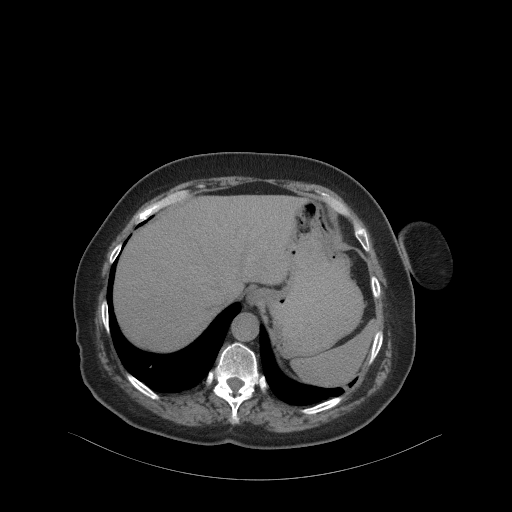

Reconstructed NATIVE CT scan (cycle consistency)

Full window (WL 1023.5, WW 4095 β†’ Low βˆ’1024, High +3071)

Lung window (WL -600, WW 1500 β†’ Low βˆ’1350, High +150)

Mediastinum window (WL 40, WW 400 β†’ Low βˆ’160, High +240)